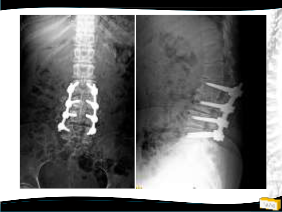

Yapılan Ameliyat

• T12-L5 tp fiksasyon

• L4 laminektomi ile L3-L4 ve L4-L5 mesafelerinin dekompresyonu

• Posterolateral grefleme

• 3 yıllık takipte sorunsuz